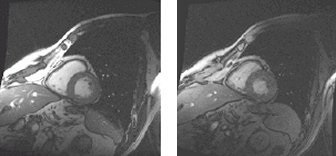

Figure 5. Off-resonance effects on cardiac FIESTA